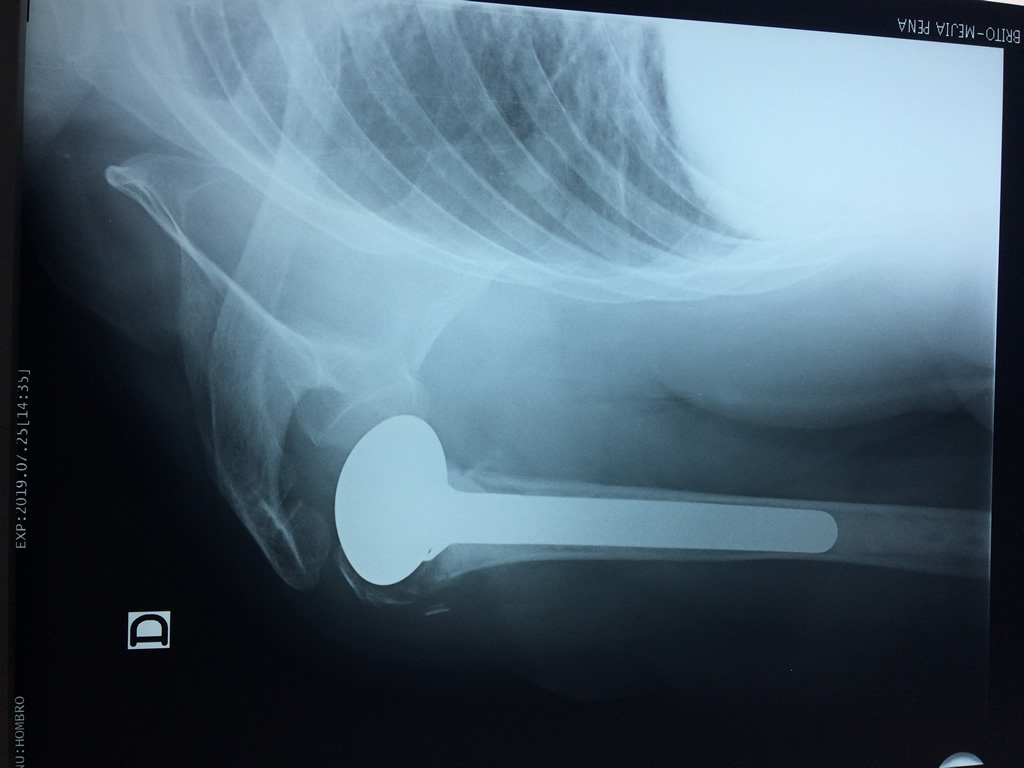

En anatomía humana, el hombro es la parte del cuerpo donde se une el brazo con el tronco. Está formado por la conjunción de los extremos de tres huesos: la clavícula, la escápula y el húmero; así como por músculos, ligamentos y tendones.

La principal articulación del hombro es la que une la cabeza del húmero con la escápula, recibe el nombre de articulación escapulohumeral y presenta dos superficies articulares, una de ellas corresponde a la cabeza del humero que tiene forma semiesférica y la otra es la cavidad glenoidea de la escápula, estas superficies están recubiertos por cartílago que permiten un movimiento suave e indoloro.